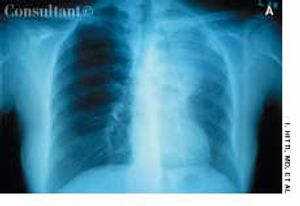

Adenocarcinoma of the Lung in a 50-Year-Old WomanByRaj K. Jain, MD,Sonia Arunabh, MDSeptember 14th 2005During the past few months, a 50-year-old woman had experienced cough, dyspnea, mild hemoptysis, and a 30-lb weight loss. She had no fever, chills, or rigors. The patient had smoked cigarettes for 30 years.